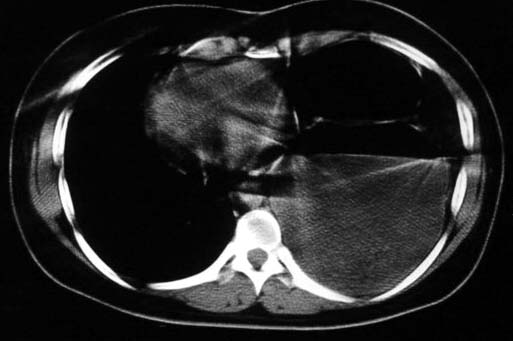

标题: CT5517:女性、24岁,反复胸痛、气促不能平卧半月。 [打印本页]

标题: CT5517:女性、24岁,反复胸痛、气促不能平卧半月。

左侧气液腔与胃腔影相连,考虑膈疝。钡餐检查有助于诊断。

我看这是膈疝,在纵隔窗第六\\七幅图像上可见胃粘膜影,再者可见两个腔影,这在液气胸是不会有的.

支持膈疝,纵隔窗内可见消化道的内容物。

“反复胸痛、气促不能平卧半月”。+影像学表现=膈疝

谨慎!喝钡透视一下吧。冒然报一液气胸,临床再穿刺引流结果把胃戳个大洞就麻烦了!

液气胸 怎么会有2 个大腔?

还是个膈疝